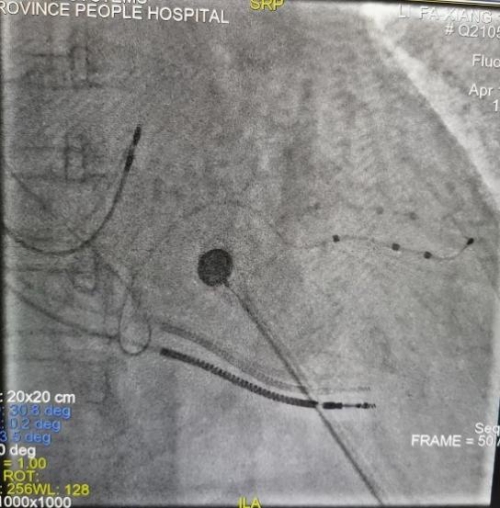

左室电极到达靶血管部位,测试参数正常

术后程控优化患者QRS波明显变窄:术前自身QRS200ms,BIV CRT(左室单部位起搏)QRS160ms,MPP CRT(左室多位起搏)QRS125ms,MPP&Sync AV QRS115ms